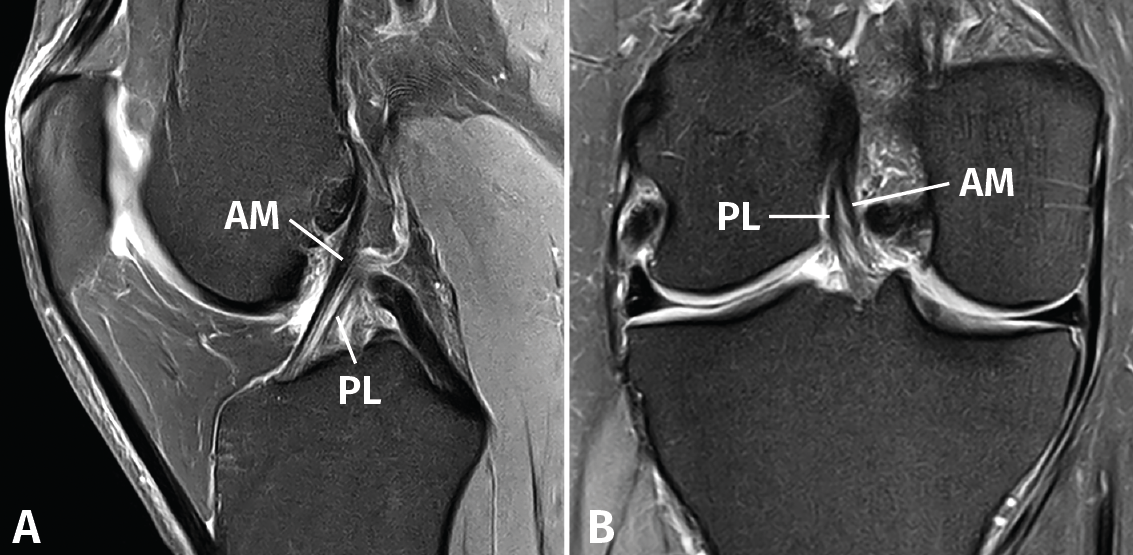

El LCA se origina en el margen medial del cóndilo femoral lateral y está formado por 2 fascículos bien diferenciados, denominados anteromedial (AM) y posterolateral (PL), en función de sus inserciones tibiales(1)(Figura 1).

Figura 1. Anatomía normal del ligamento cruzado anterior (LCA). Esquemas sagital (A) y coronal (B) que ilustran la anatomía fascicular del LCA. AM: fascículo anteromedial; PL: fascículo posterolateral.

El protocolo de estudio por RM debe incluir secuencias en densidad protónica (DP) con supresión selectiva de la grasa en los 3 planos ortogonales. La valoración del LCA debe realizarse combinando la información de todos los planos. En el plano sagital, con frecuencia resulta complicado diferenciar tanto la anatomía fascicular como la inserción proximal. Los cortes coronales y axiales sucesivos son los más útiles para valorar con precisión la anatomía fascicular y las lesiones parciales del LCA (Figura 2).

Figura 2. Anatomía normal del ligamento cruzado anterior (LCA) en secuencias convencionales de resonancia magnética (RM). A: corte sagital potenciado en densidad protónica (DP) con supresión grasa que muestra en toda su extensión el trayecto del fascículo anteromedial (AM); B: corte coronal de RM potenciado en DP con supresión grasa que muestra la anatomía bifascicular. PL: fascículo posterolateral.